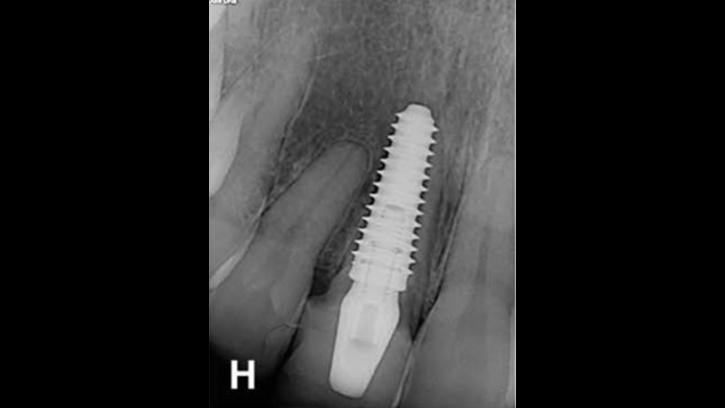

Clinical case: Bone filling into the bottom of deepest thread at 8.0mm AnyRidge fixture

- Courtesy of Dr. Kwang Bum Park -

AnyRidge, Knifethread ,extraction socket, ,initial stability ,Allograft, ,osseointegratio ,Dr. Kwang Bum Park, , Mandibular, Single replacement, AnyRidge, Mega-oss,

Implant system-AnyRidge, Regeneration-Mega-Oss

How can primary stability be increased?

Primary stability is especially important in the case of poor quality bone. The instability of dental implants results in fibrous encapsulation and failed osseointegration (Lioubavina-Hack, et al. 2006). One method for increasing primary stability is modifying the surgical technique for implant placement. Studies have reported that the undersized surgical technique, which uses a final drill diameter smaller than the diameter of the implant, results in a higher primary stability when compared with the press-fit technique (Tabassum, et al. 2009, Tabassum, et al. 2010a).

Ti implants with a deeper thread depth provide a higher surface area, which is advantageous for increasing stability in areas of poor quality bone (Abuhussein, et al. 2010). Ti implants with deeper thread depths also facilitate an increased load and mechanical interlocking with poor quality bone.

Another method increasing the primary stability is to change the implant design, such as the shape of the implant body and thread, length, and diameter. Various thread designs for taper implants and other dental implant designs have already been reported to effect the primary stability. Taper implants also show a higher primary stability than cylindrical implants (Kim, et al. 2009, Sakoh, et al. 2006, Wilmes, et al. 2008).

Meanwhile, dental implants with a long length or wide diameter show a significantly increased insertion torque (Kim,et al. 2009, Wilmes, et al. 2008). Plus, dental implants without self-tapping blades have a higher primary stability than implants with self-tapping blades (Kim et al. 2011).